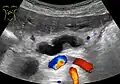

Ultrasonography of a dilated pancreatic duct (in this case 9mm) due to pancreatic cancer. -

Compression, obstruction or inflammation of the pancreatic duct may lead to acute pancreatitis. The most common cause for obstruction is the presence of gallstones in the common bile duct, a condition called choledocholithiasis. Obstruction can also be due to duodenal inflammation in Crohn's disease.[7] A gallstone may get lodged in the constricted distal end of the ampulla of Vater, where it blocks the flow of both bile and pancreatic juice into the duodenum. Bile backing up into the pancreatic duct may initiate pancreatitis.[8] The pancreatic duct is generally regarded as abnormally enlarged if being over 3 mm in the head and 2 mm in the body or tail on CT scan.[9] Pancreatic duct or parts of pancreatic duct can be demonstrated on ultrasound in 75 to 85% of people.[10]